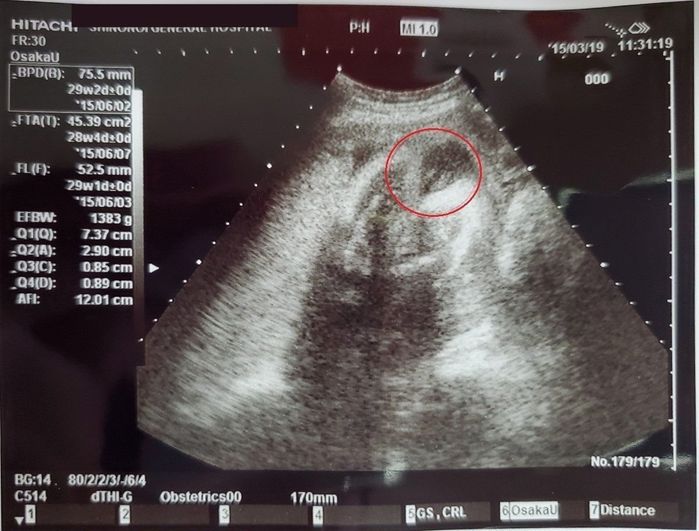

妊娠28週目のエコー写真 - やっと性別判明!?

女の子っぽい!そう思いました。…とはいえ、私の通っていた病院は性別を教えない方針で、ヒントはもらえるものの自分で判断しなければなりません。今なら「女の子」と断言できるのですが、ネットなどで色々調べたものの、当時の私の知識では確定に至りませんでした。「性別が確定したら、赤ちゃんグッズを選んだり、名前を決めたりしよう!」と意気込んでいたので、出産するまでは「女の子かな?」という仮定のまま、ずっとモヤモヤしていました。(今となっては、自分の中で笑い話ですが…!)

※写真はお尻が正面を向いているアングルです。赤マル部分が、病院側でくれたヒントでした。